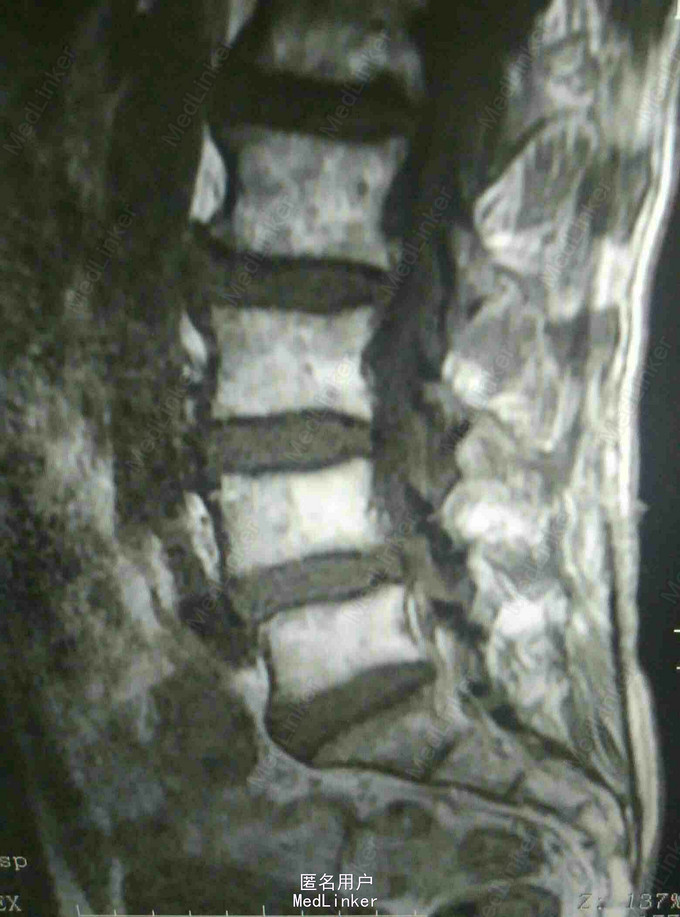

反复腰痛5年,加重伴跛行10余天 患者老年男性,5年前无明显诱因出现腰痛,休息后缓解,数年来反复发作,自行外用膏药对症治疗。近10余天来患者腰痛明显加重,伴跛行,右下肢疼痛,于当地医院就诊摄片提示腰椎退变,为进一步治疗入我院。

查体:腰4~5棘突及骶部压痛,无明显叩击痛,右大腿外侧疼痛,右足背外侧感觉减退,双下肢肌力正常,双侧直腿抬高实验阴性。 辅查:外院X线片提示腰椎退变 我院核磁提示腰4-5关节突增生内聚,椎间盘后突压迫硬膜囊及神经根

诊断:腰椎管狭窄 治疗:腰椎后路减压植骨内固定术